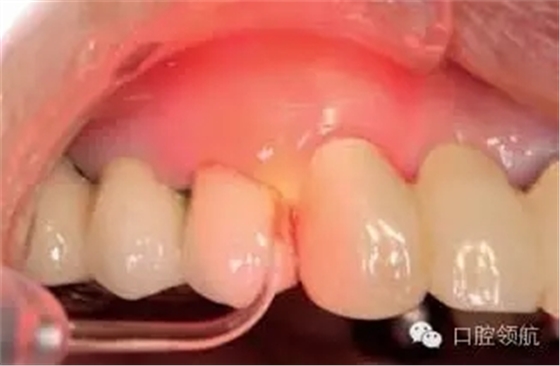

現(xiàn)在的牙周治療方法,是以機(jī)械性治療中加入抗生素等化學(xué)療法形成的機(jī)械化學(xué)治療為中心的方式。近年來(lái),抗菌性的光線力學(xué)治療法(a-PDT)逐漸被關(guān)注(圖3、圖4)。a-PDT是指感光性藥物在特殊光線的照射下被激活而產(chǎn)生出活性氧的方法。不僅對(duì)細(xì)菌而且對(duì)病毒以及真菌也是有效的,同時(shí)具有無(wú)耐藥細(xì)菌的出現(xiàn)和過(guò)敏等副作用的優(yōu)點(diǎn)。本病例在對(duì)患者進(jìn)行了充分地說(shuō)明,并得到同意后,實(shí)施a-PDT治療1周,患者的不適感消失了(圖5)。

圖4 用670nm紅色光照射的口內(nèi)所見(jiàn)。

圖5 2周后的口內(nèi)情況,周?chē)例l出血消失,狀態(tài)穩(wěn)定。